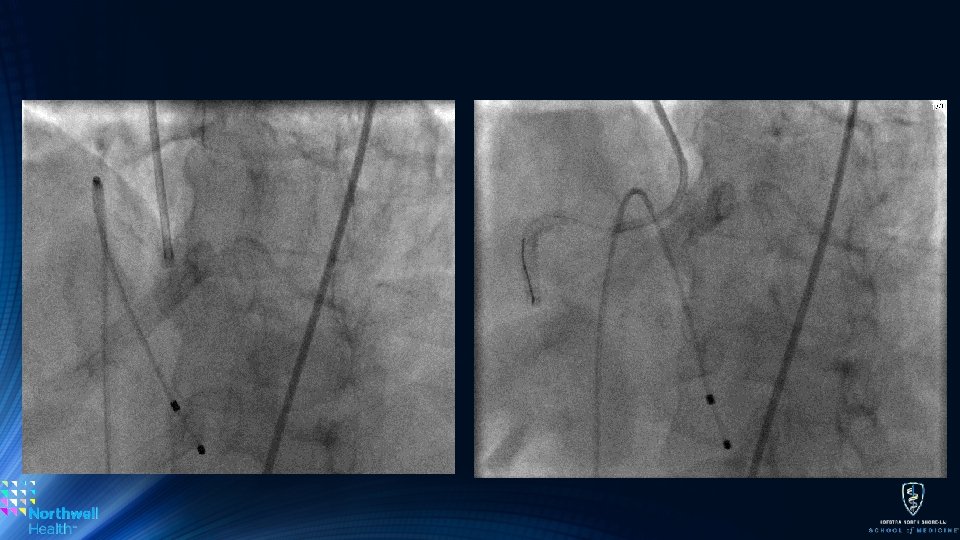

Concentric Calcium or Ostial Lesions • Very tight Concentric Calcium: • More concentric and tight • RA front ‘cuts’ thus engages lesions better than OA • RA can also stall and be stuck if a pecking style in not employed • Ostial Lesions (ie. o. RCA and o. LM) • RA remains the ideal choice due its concentic rotation • OA may damage the aorto-ostial junction – technique is key, • If OA is used it can be placed past the lesion and retrograde atherectomy can be performed